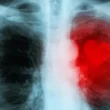

يُعد سرطان الرئة أحد أخطر أنواع السرطانات، وغالبًا ما يتطور بصمت في مراحله الأولى دون ظهور أعراض واضحة. لكن إدراك العلامات المبكرة يمكن أن يحدث فرقًا كبيرًا في التشخيص والعلاج.

في هذا المقال، نُسلط الضوء على 7 أعراض لسرطان الرئة قد تكون مؤشرًا لوجوده. التعرف على هذه الأعراض يُمكنك من طلب المساعدة الطبية في الوقت المناسب، مما يعزز فرص الشفاء.